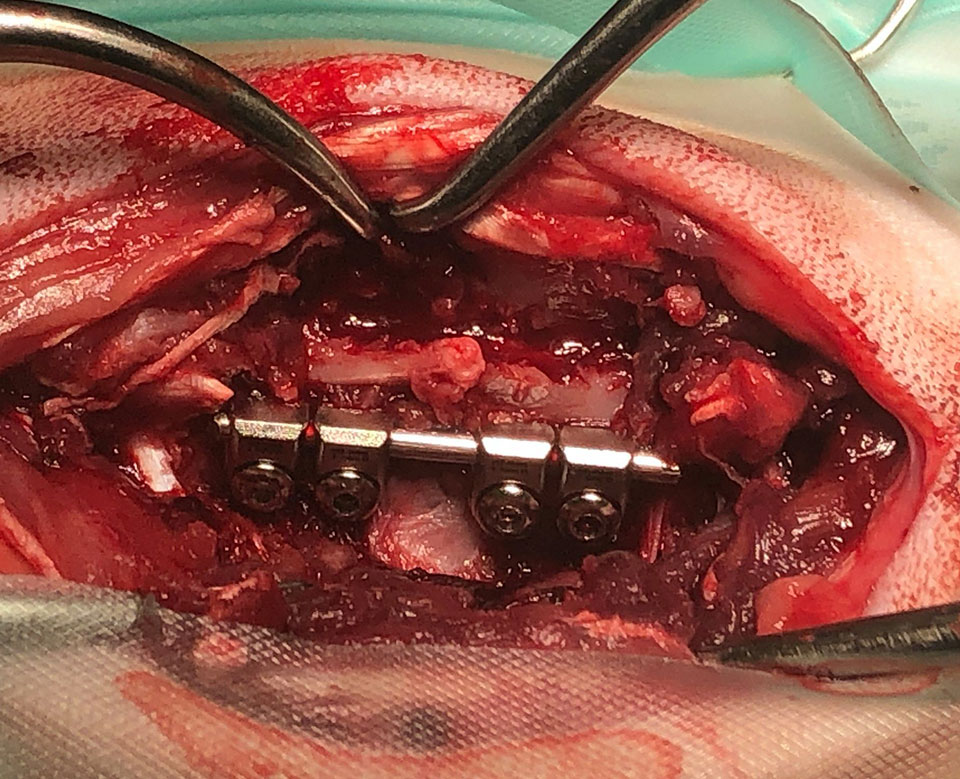

Mini SOP-LC (for 2,0mm srews) were used for stabilisation of vertebral luxation and fracture in cat.